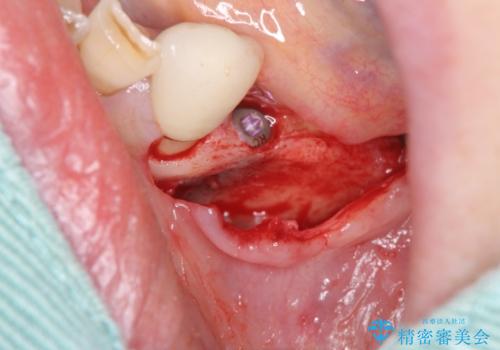

入れ歯を外し、またしっかりと噛んで食事を楽しめるようになるためにインプラントによる治療を計画します。

- 91万円(ストローマンインプラント×2・骨造成・チタンカスタムアバットメント×2・フルジルコニアクラウン×3)費用は治療当時の料金となります

- 外科手術のため、術後に痛みや腫れ、違和感を伴います